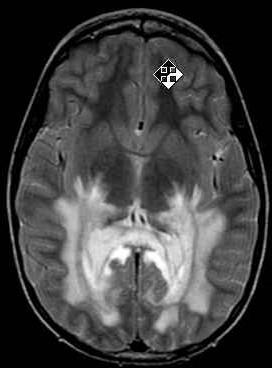

• Non-specific subcortical WM, periventricular sparing

Non-specific subcortical WM, periventricular sparing + globi pallidi / thalami + globi pallidi / thalami

• Lactate peak on MRS (typical of mitochondrial disorders)

Lactate peak on MRS (typical of mitochondrial disorders)